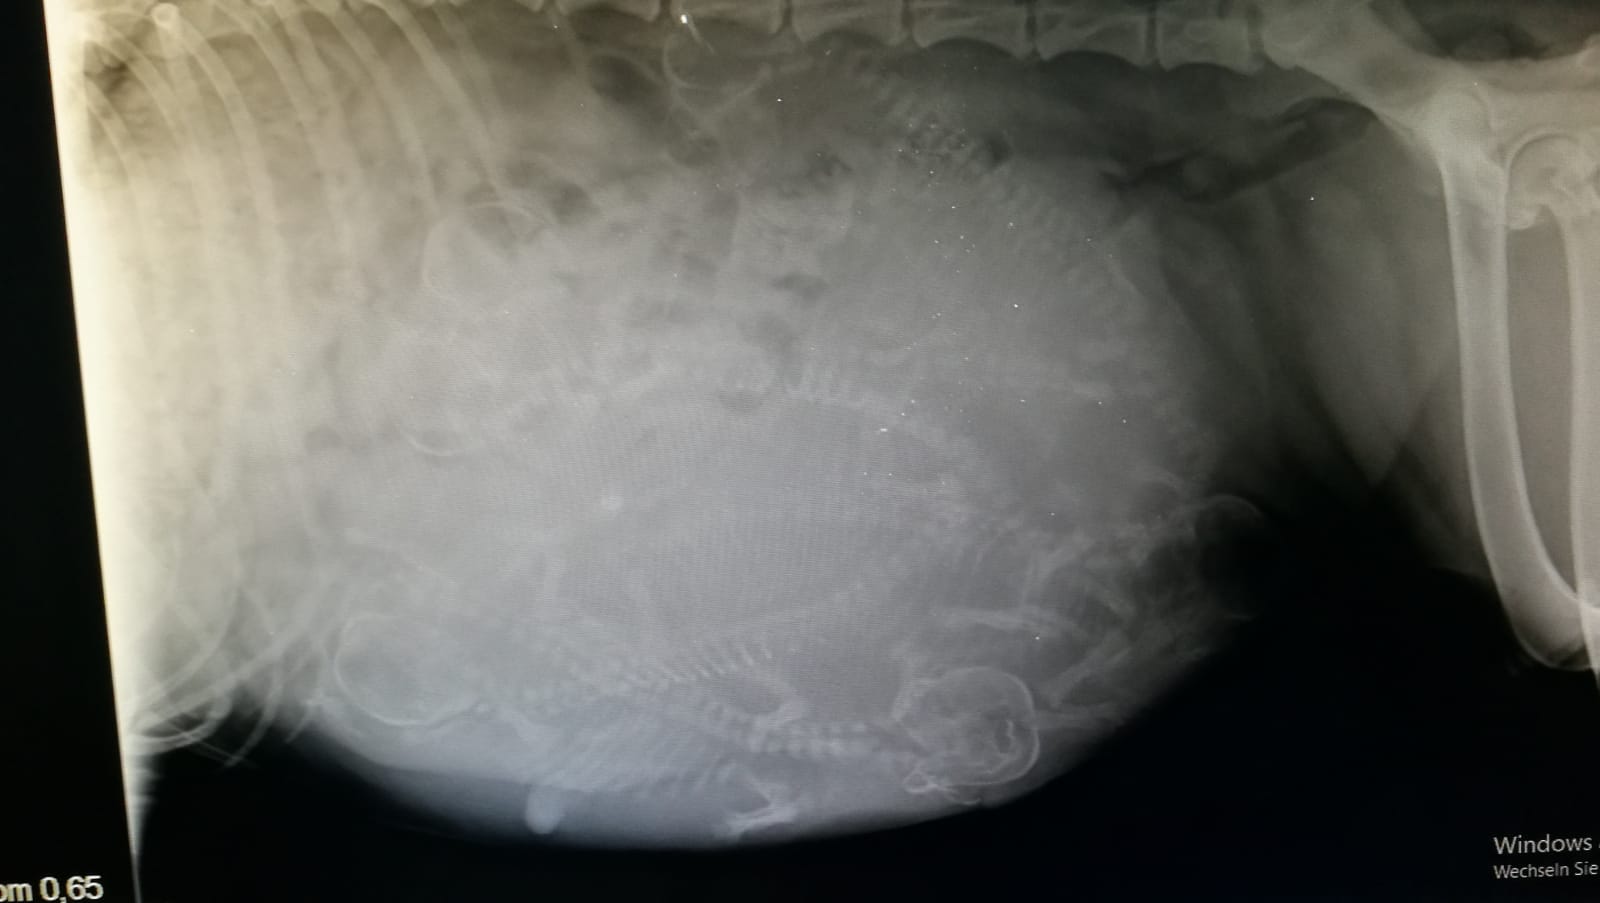

Röntgen: 6 Welpen